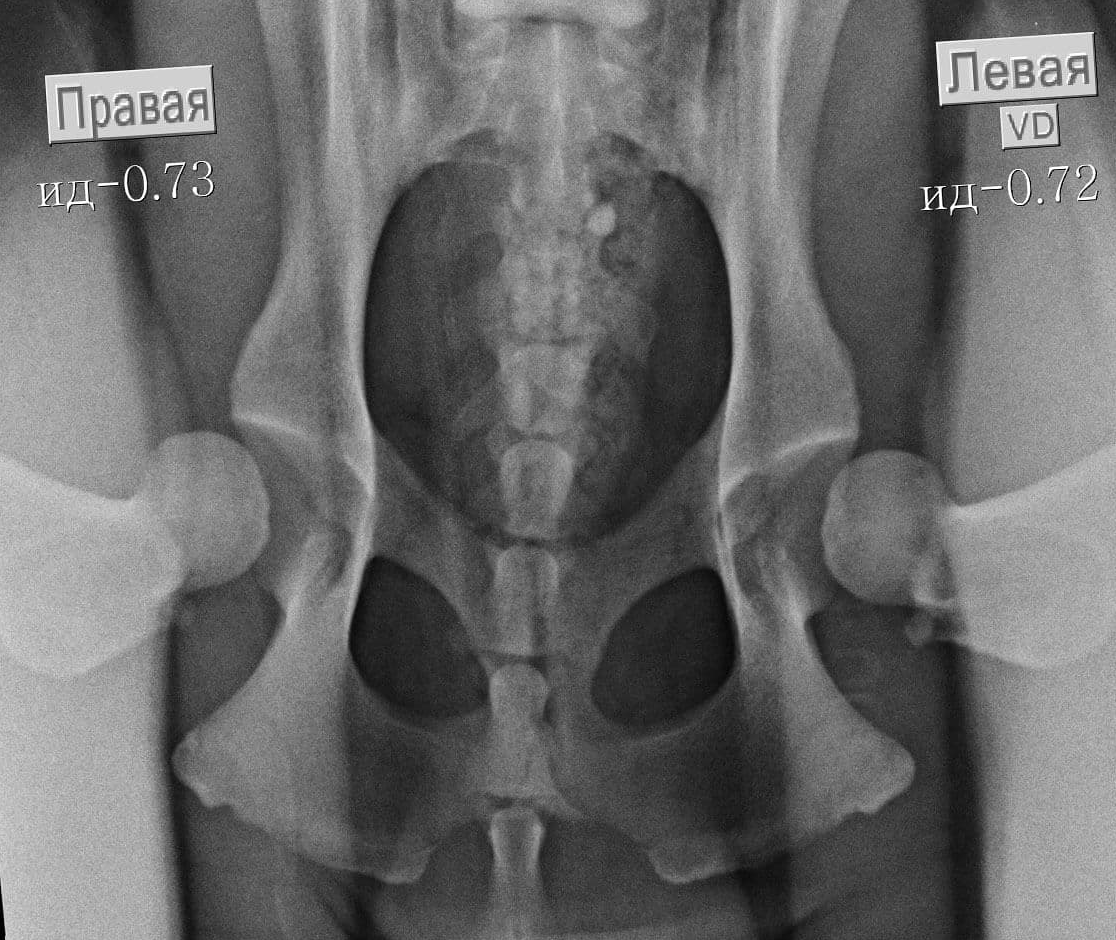

У доберманов крепкое здоровье, но, как и у всех пород, есть недостатки: плохая свертываемость крови, проблемы со зрением, дисплазия тазобедренных суставов (особенно у пожилых собак), заболевания щитовидной железы и сердечной мышцы. Это альбинизм или даже рак.

- Дисплазия тазобедренных суставов. В настоящее время это редкость, так как собак с этим заболеванием не допускают к разведению.